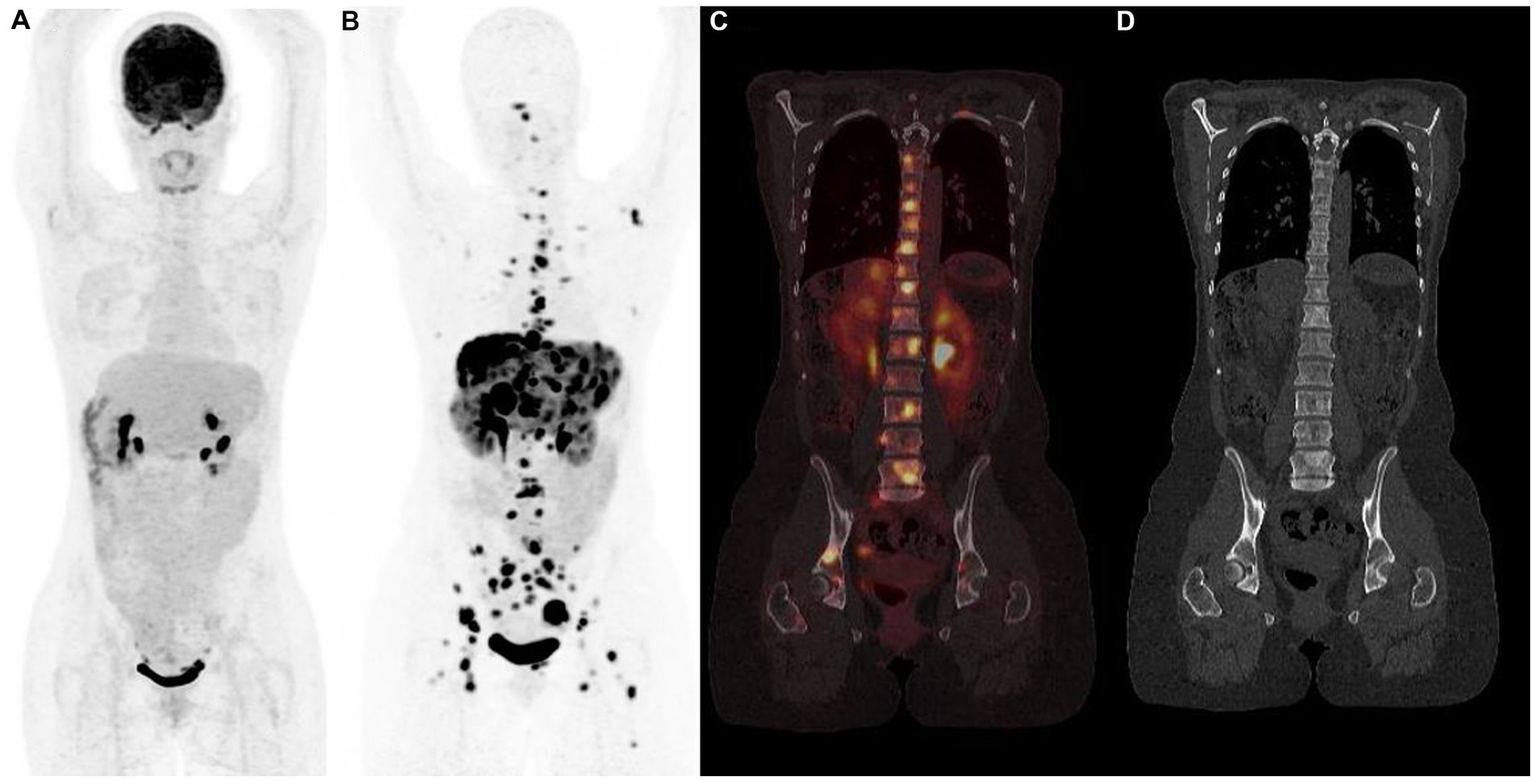

Figure 4

18F-FDG (A) and 68Ga-DOTATOC (B–D) PET/CT results (anterior MIP, coronal PET/CT, coronal CT) in a 48 years-old woman with grade 2 metastatic pancreatic neuroendocrine tumor showing multiple bone sclerotic metastases characterized by intense and pathologic 68Ga-DOTATOC uptake. 18F-FDG PET/CT failed to detect metastatic spread.